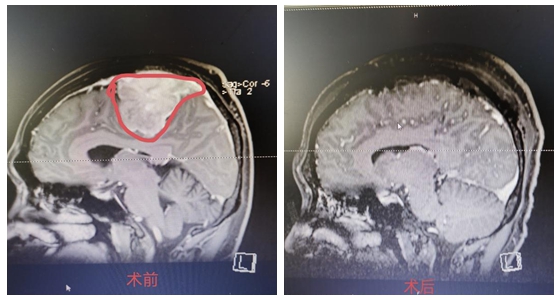

手术前后对比图

4月24日,经过9个多小时的手术,杨先生的肿瘤成功全部切除。术后,杨先生恢复良好,除术前肢体功能稍差的右下肢肌力较差外,其余肢体肌力正常,不日即可康复出院。